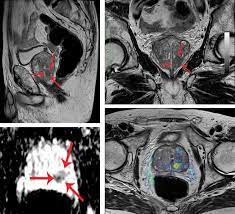

The Importance Of Mri S In Diagnosing Prostate Cancer Rosetta Radiology

The Importance Of Mri S In Diagnosing Prostate Cancer Rosetta Radiology from rosettaradiology.com